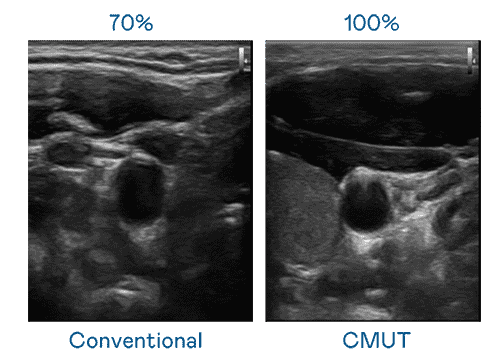

CMUT 技术是一种用电容式微机电元件来产生超音波讯号的技术。。与传统 PZT 压电式技术相比,,,CMUT 频宽增加 30%,,,,更宽频的超音波讯号让影像解析度大幅提升,,,,是实现高影像品质医疗超音波扫描、、、、促进精准医疗发展的关键技术。。。。

大频宽带来超清晰影像

超音波影像的解析度高低,,首先取决于探头能发出的讯号频宽。。PG国际 CMUT 可提供高清晰的超音波讯号,,,提供高频宽、、高灵敏度、、、、影像纹理细节更高的超音波影像,,,,协助医护人员缩短影像判读时间及利用精准的医疗影像进行诊断。。